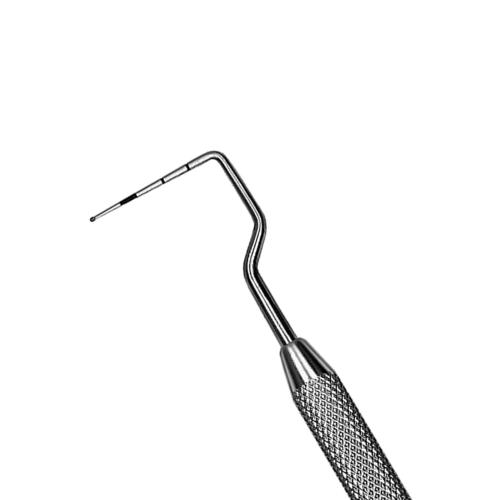

Parodontometro Novatech #NT11 Qulix 3-6-8-11

Parodontometro Novatech #NT11 Qulix 3-6-8-11

Parodontometro Novatech #NT11 Qulix 3-6-8-11

Parodontometro Novatech #NT11 Qulix 3-6-8-11

Cod

PCPNT11

PCPNT11

Novatech, color-coded probe.

46,80 €

Unique right angle design for improved adaptability in posterior regions. QulixŖ probes are color-coated with accurate, smoothly finished black markings which will not chip, flake or fade.